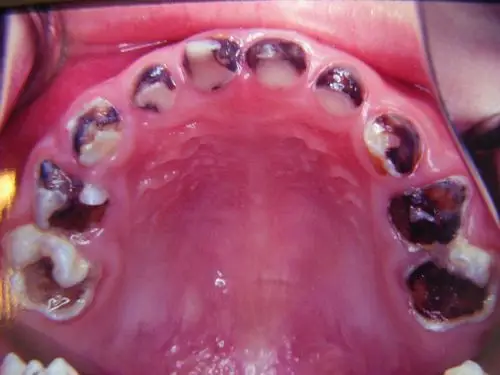

严重龋齿的图片_有来医生